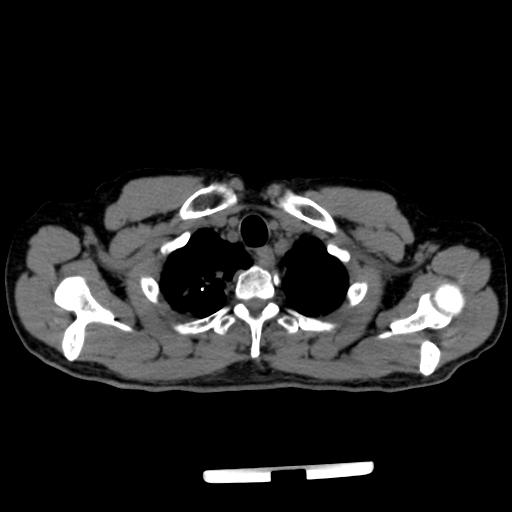

CT49722:胸部CT会诊24394

本帖最后由 cefcmj 于 2015-1-8 18:03 编辑 患者:男,61Y,咳嗽、咳痰1+天,咯血一次,双肺呼吸音粗。

两肺尖见少许条索影、斑片影及点状钙化影,右上肺纵隔旁见数个类圆形无肺纹理区;另两肺见数个小结节影,右侧胸膜局限性增厚。肝右叶顶部见小圆形低密度影。

1、两上肺少许陈旧性结核灶(右侧明显)伴右上肺局限性肺气肿;两肺少许感染;

2、两肺小结节影,结核灶可能性大,建议随访;

3、右侧胸膜局限性增厚;

4、肝右叶顶部小圆形低密度影,囊肿可能。

两肺上叶尖段陈旧性病变,合并肺大泡及两肺间质增生。肺窗第一层主支气管内右下壁不规则突入腔内,痰液?